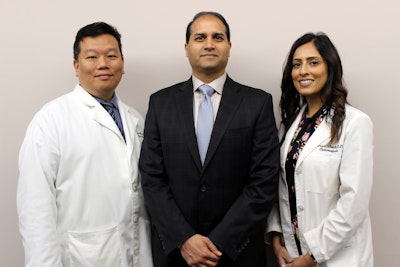

Have you grown weary of the hassle and expense associated with glasses and contact lenses? Safe, effective and nearly painless procedures are available to sharpen vision and do away with the need for cumbersome visual aids. At Sheth-Horsley Eye Center, our specialists perform a range of refractive surgeries to improve our patients' eyesight. If you are interested in learning more or would like to schedule an examination with Dr. Nilesh M. Sheth or Dr. Robert Kupsc, please take the time to fill out our simple online contact form.